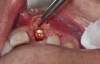

(45.) A patient presented for the replacement of the maxillary left central incisor with a bonded pontic made from the natural tooth, which was removed.

Figure 45

(46.) Occlusal view of the implant after placement.

Figure 46

(47.) The primary stability of the implant was confirmed to be sufficient for immediate loading.

Figure 47